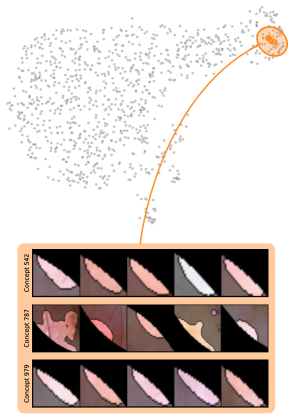

Model Perspective

Next, we apply bias identification approaches from the model perspective by identifying outlier neurons based on activation pattern via DORA and relevance pattern by clustering pair-wise cosine distances between concept relevance scores. We focus on latent activations and relevances after the third residual block. DORA uses a distance function based on how neurons activate upon each others n-AMS, achieving high similarity when neurons activate upon similar input signal. A 2D visualization of the resulting distance matrix is shown in Fig. 6 (bottom left). Identified outlier concepts include ruler () and (white) hair (). We further compute pairwise cosine distances between latent relevance scores , aggregated over spatial dimensions, and apply UMAP to embed the resulting distance matrix in . This results in high similarity between neurons (concepts) that the model uses similarly for predictions. The concept clustering is visualized in Fig. 6 (bottom right), highlighting two outlier clusters focused on rulers () and blueish tint ().